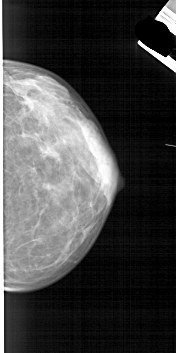

A_1841_1.LEFT_CC

LEFT_CC LINES 4636 PIXELS_PER_LINE 2326 BITS_PER_PIXEL 12 RESOLUTION 43.5 OVERLAY